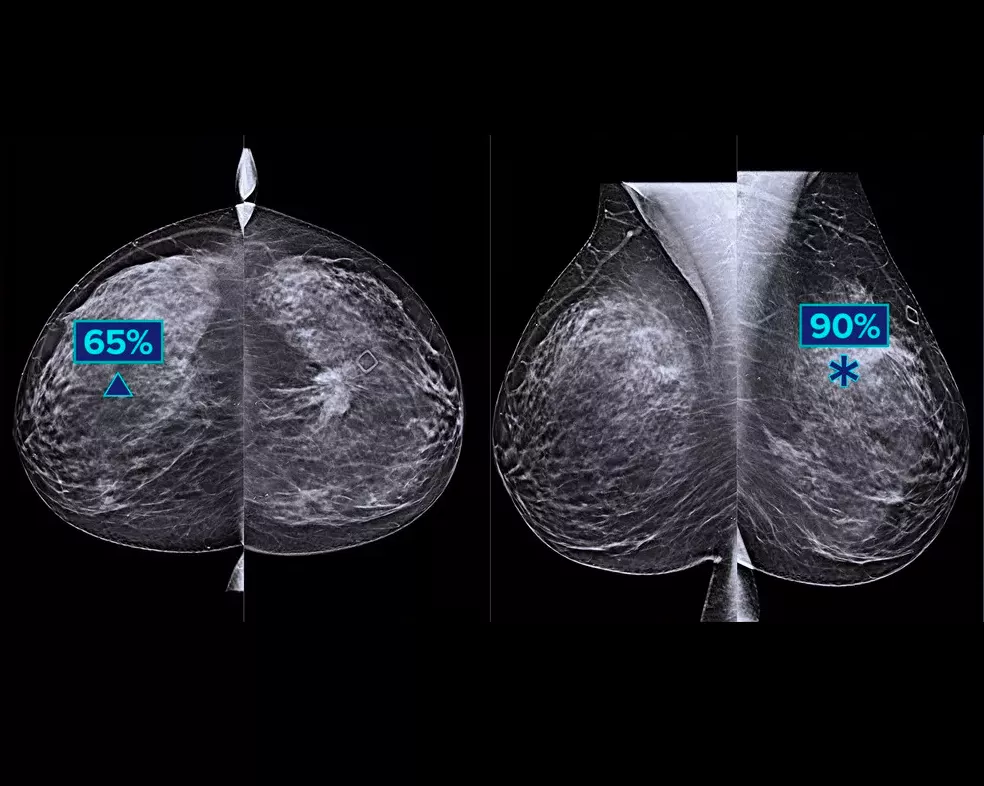

Un algoritmo di deep-learning studiato per coadiuvare le prestazioni diagnostiche dei medici radiologi e individuare i tumori al seno1-3 dalle immagini di tomosintesi ottenute con i sistemi mammografici Dimensions® Hologic. L'algoritmo individua le lesioni probabilmente riconducibili a un tumore della mammella, analizzando ogni sezione della serie di immagini di tomosintesi. Le aree sospette vengono evidenziate sulla stazione di lavoro del medico radiologo per una lettura immediata e un ausilio nell'interpretazione.

Uno studio mostra un miglioramento del 9% della sensibilità di lettura.1.2 Funziona su immagini di tomosintesi standard e ad alta risoluzione, sovrapponendo le informazioni su SmartSlice 3DQuorum e immagini 2D sintetiche.

L'algoritmo cerca 3 gruppi principali di lesioni sospette: calcificazioni, masse, densità con distorsioni e le loro combinazioni. I risultati possono variare in base alla stazione di lavoro usata per la refertazione.

L'integrazione sulla postazione di acquisizione consente di contrassegnare i casi ad alto rischio per una lettura immediata. Le metriche a livello di caso aiutano a classificare i casi per priorità di lettura.

Hologic ha condotto uno studio su più lettori e più casi (MRMC) per verificare le prestazioni dell'algoritmo Genius AI.3